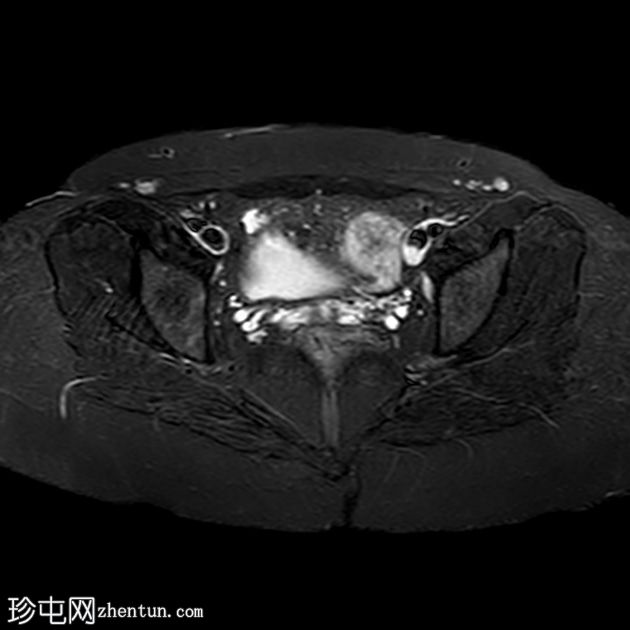

轴位

STIR序列

盆腔两侧可见两个残角,位于双侧卵巢尾侧。可见一条水平带连接两个残角。左侧残角呈腔状,右侧残角呈非腔状。

可见宫颈阴道发育不全,从两个残角延伸出少量发育不良的宫颈组织带。

本病例展示了一种 Mayer-Rokitansky-Küster-Hauser 综合征 (MRKH),其特征为子宫缺失和双侧残角;左侧子宫角呈腔状,右侧子宫角呈非腔状。子宫角位于盆腔两侧,双侧卵巢尾侧,并由一条水平带连接。该病伴有宫颈阴道发育不全。